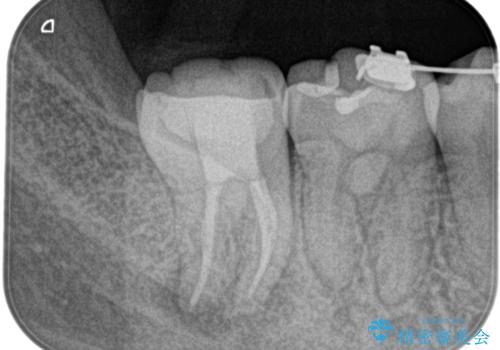

- 奥の歯茎にニキビみたいなものができたことを主訴に来院されました。

来院時は特に痛みはありませんでしたが、5年ほど前は痛みがあり、他院で虫歯の治療をしたことがあるとのことでした。

歯髄検査をし、歯髄壊死と診断できたため治療を介入しています。

咬合面の修復材料を除去すると内部に細菌の塊である多量のカリエスが残存しており、それが原因で歯髄が壊死したと考えられます。

治療中、細菌の除去を徹底的に行えるように顕微鏡とラバーダム(ゴムのシート)を用いて行いました。